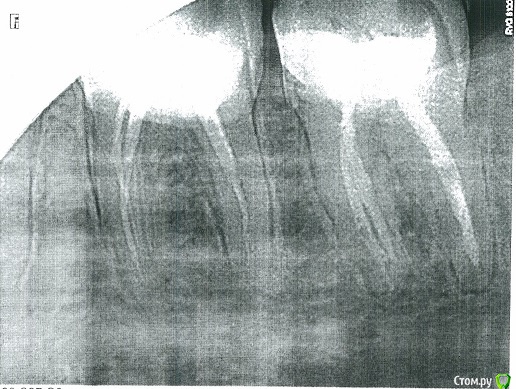

Sloboda Опубликовано 20 февраля, 2017 Поделиться Опубликовано 20 февраля, 2017 Здравствуйте! Проблема такая: был пролечен по пульпиту 36 зуб, запломбированы каналы, поставлена пломба и штифт. Зуб до этого не болел и вообще никак не беспокоил, просто было затемнение рядом со старой цементной пломбой - решили пломбу поменять - под ней сюрприз - хронический пульпит. Через месяц после лечения зуб стал реагировать при приеме пищи (реакции только на нагрузку; реакции на температуру отсутствовали и отсутствуют вообще) - слабо пульсировать. Стоматолог сказал, что это нормально и должно само пройти. В течении полугода, такие пульсации при приеме пищи в зубе проявлялись периодически, но сильно не беспокоили. На очередном приеме, на жалобы по поводу пульсации 36 зуба, стоматолог сказал, что, возможно, это из-за завышенной пломбы - пломбу подпилили. И вот уже 4 дня зуб сильно болит следующим образом: при притрагивании к зубу языком/пальцем возникает сильная пульсирующая боль, невозможно сомкнуть челюсть, жевать на стороне больного зуба невозможно, припухла десна, также опух лимфоузел на стороне больного зуба. Соседние зубы - 7 (также пролечен по пульпиту много лет назад) и 5 никак не реагируют, на них можно спокойно жевать и т.д. Т.е. локализация боли чисто в 36 зубе. Делали рентген 36 зуба, врач сказал, что все прекрасно, периодонтита нет, каналы пролечены хорошо. Стучали по зубу (и с верху, и с боку) - болевой реакции нет. Проверяли прибором каким-то проводящим электричество (не помню как называется), сказали, что остатков нерва нет, т.к. нет никакой болевой реакции при подаче тока нет. Но зуб-то продолжает болеть! Боль несколько снизилась после принятия ципролета (2 таблетки). Врач сказал, что это скорее всего или десна или опять же, завышенная пломба (пломбу подпилили еще раз), но если боль не пройдет - придется зуб вскрывать. На мой взгляд, есть непролеченный участок в канале, думаю, это он воспалился + симптомы очень сильно похожи на периодонтит. Хотелось бы узнать ваше мнение - что это такое и что с эти делать. Заранее благодарю за помощь. К сожалению, снимков лучшего качества пока нет, т.к. формат rvg нигде не открывается, завтра приложу скриншот улучшенной версии снимка. На первом снимке, сделанном на пеленку видна только часть 36 зуба), сам снимок был сделан полгода назад. Второй снимок сделан сегодня. Ссылка на комментарий

red_butler Опубликовано 20 февраля, 2017 Поделиться Опубликовано 20 февраля, 2017 Требуется повторное лечение корневых каналов шестого зуба Ссылка на комментарий